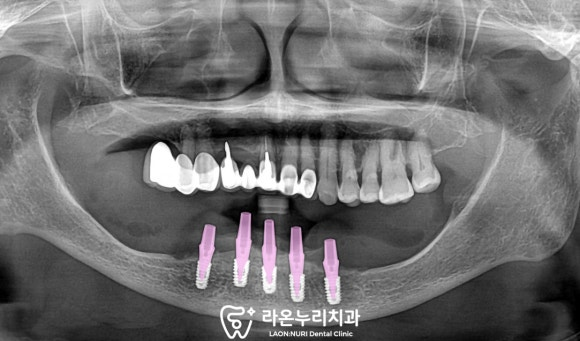

■ 3. 수술 과정

모든 사전 준비가 마무리되었다면

이제는 픽스처를 심어야겠죠?

위 사진은 서지컬 리포트라 부르는데요,

치아 번호(치식), 임플란트의 브랜드,

길이, 폭경, 식립 위치, 하치조 신경까지의 거리

같은 여러 중요 정보가 담긴 요약본입니다.

디지털 모의 시술로 예측한 결괏값이

적혀있는 중요한 자료이죠.

서지컬 리포트를 바탕으로

식립이 마무리된 모습입니다.

좁고 낮아진 치조골의 상태를 고려하면서

초기고정력을 잘 받을 수 있는 부위이자,

하치조신경과 이공의 앞쪽으로 하여

안전한 위치로 심어드렸습니다.

그리고 당일에 어버트먼트까지 연결해드린 모습입니다.